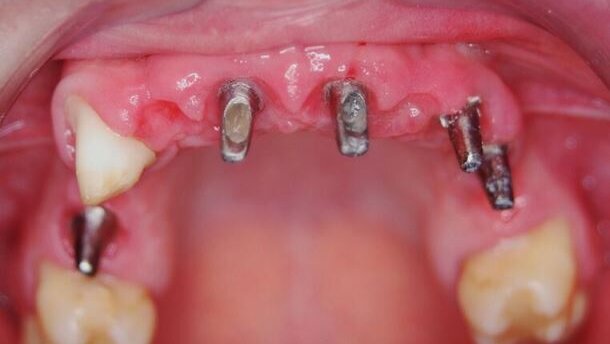

Mężczyzna, l. 44 zgłosił się w celu konsultacji z powodu problemów estetycznych i funkcjonalnych przedniego odcinka szczęki (Ryc. 12 i 13). Z powodu ruchomości zębów 12, 11, 21, 22 uniemożliwiających wykorzystanie ich w konwencjonalnej protetyce, podjęto decyzję o ich usunięciu. Jako rozwiązanie tymczasowe uzupełniające powstałe braki zębowe zastosowano natychmiastową protezą ruchomą o zredukowanej płycie podniebiennej.

Po okresie gojenia tkanek miękkich przystąpiono do zabiegu pogrążenia 3 wszczepów śródkostnych w pozycji zębów 12, 21, 22 wraz z jednoczasową augmentacją deficytów kości xenograftem z resorbowalną błoną zaporową (Ryc. 14 i 15). Pomimo wystarczającej ilości miejsca, nie zdecydowano się na wprowadzenie 4 wszczepów śródkostnych

i wykonanie 4 pojedynczych implantokoron. Podyktowane to było dużym prawdopodobieństwem powstania czarnych trójkątów, znacznie obniżających walory estetyczne uzyskanego efektu leczenia. W celu uzyskania satysfakcjonującego efektu estetycznego i funkcjonalnego, jako docelowe uzupełnienie protetyczne zastosowano 4-punktowy most metaloceramiczny cementowany na 3 standardowych łącznikach protetycznych (Ryc. 16 i 17).